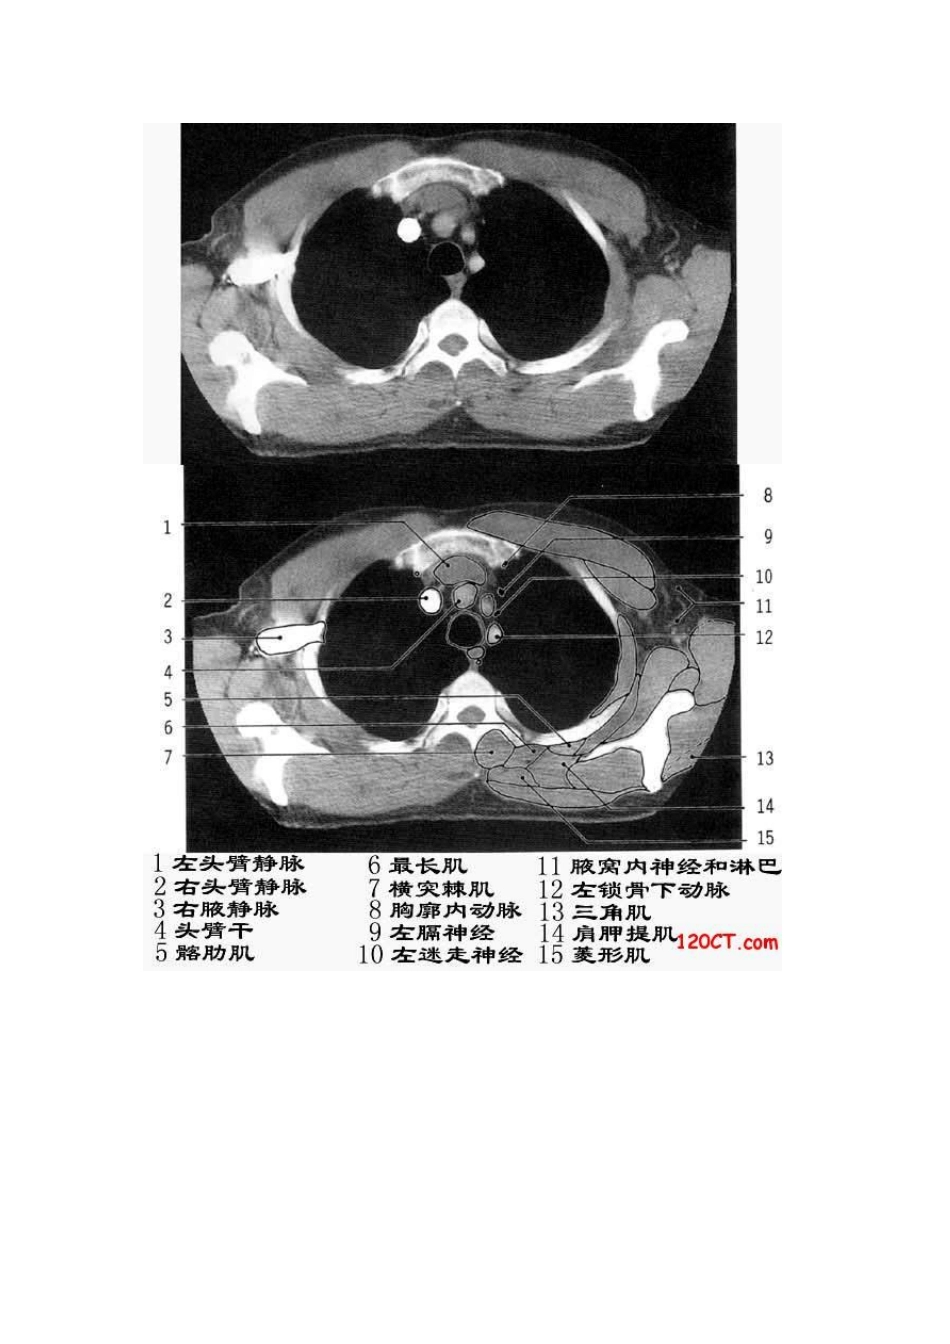

胸部CT解剖(软组织窗)